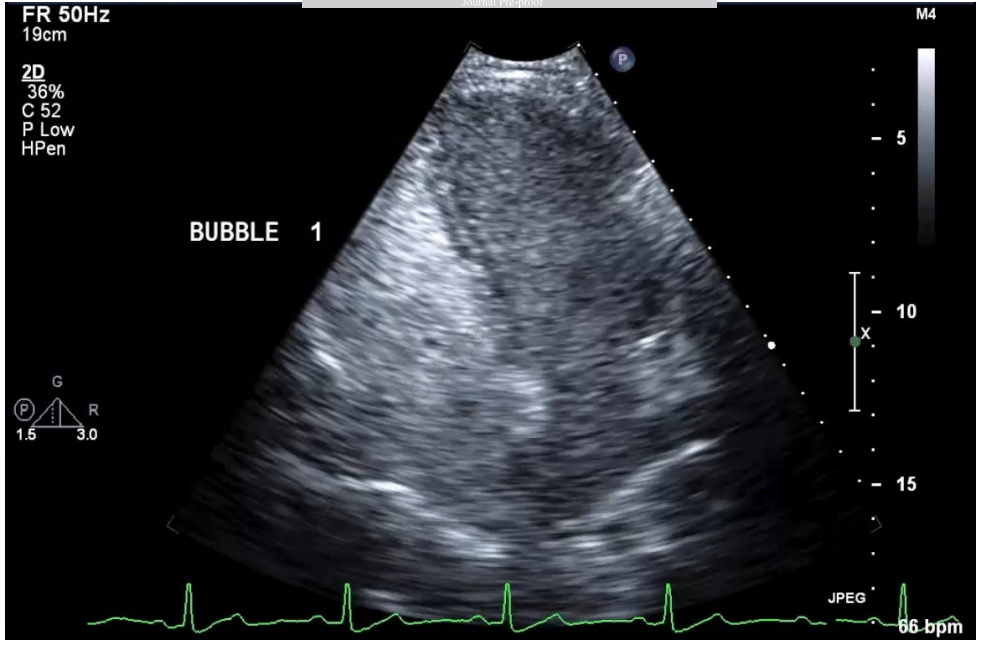

TTCE在检测肺右向左分流方面表现出高敏感性和阴性预测值。现行指南建议阴性者每5-10年复查,但在青春期或妊娠期间应增加监测频率。需要注意的是,高级别分流和已知有大型未治疗PAVMs的病例需要经验丰富的操作者仔细评估,以避免漏掉具有临床意义的分流(图1)。在未确诊HHT的患者中,区分肺内分流和心内分流变得至关重要;肺内分流可通过左心房出现气泡前有四个心动周期的特征性延迟来识别。研究显示约6-25%的正常人群也可能出现右向左分流,这增加了结果判读的难度。不同指南对TTCE在栓塞后监测中的使用建议存在差异,BTS认为其可用于筛查,而HHT国际指南则要求阳性结果必须经CT确认(图2)。

图2.一名HHT患者的3级TTCE图像。根据麻省总医院HHT方案进行气泡对比剂研究。对比剂级别:3级(大量气泡,>100个)。首次出现的时间是右心显影后3次心跳。激动盐水在3次心跳后早期从右心房到左心房的交叉出现提示可能存在心房间分流,尽管观察到对比剂气泡从肺静脉流出支持肺内分流的判断。分流较大。可见左心显影。